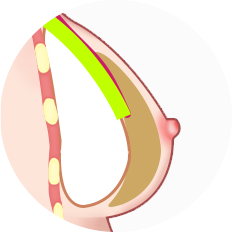

เทคนิคแบบ Dual Plane แบ่งออกเป็น 3 ประเภทใหญ่ ๆ ขึ้นอยู่กับระดับของการสร้างพื้นที่ใต้เยื่อหุ้มเซลล์

ผ่าตัดส่วนล่างของกล้ามเนื้อหน้าอกส่วนบน

เมื่อกรีดกล้ามเนื้อออก เนื่องจากแรงดึงของกล้ามเนื้อ ทำให้ส่วนบนของกล้ามเนื้อหดตัวและด้านล่างของกล้ามเนื้อจะยึดติดกับด้านล่าง

ใส่ซิลิโคนระหว่างกล้ามเนื้อที่ถูกกรีด ส่วนบนของซิลิโคนอยู่ด้านล่างของกล้ามเนื้อหน้าอก ส่วนล่างของซิลิโคนอยู่ด้านบนของกล้ามเนื้อหน้าอก

วิธีการใส่ท่อนบนของซิลิโคนลงไปใต้กล้ามเนื้อ และท่อนล่างลงไปใต้เยื่อกล้ามเนื้อ